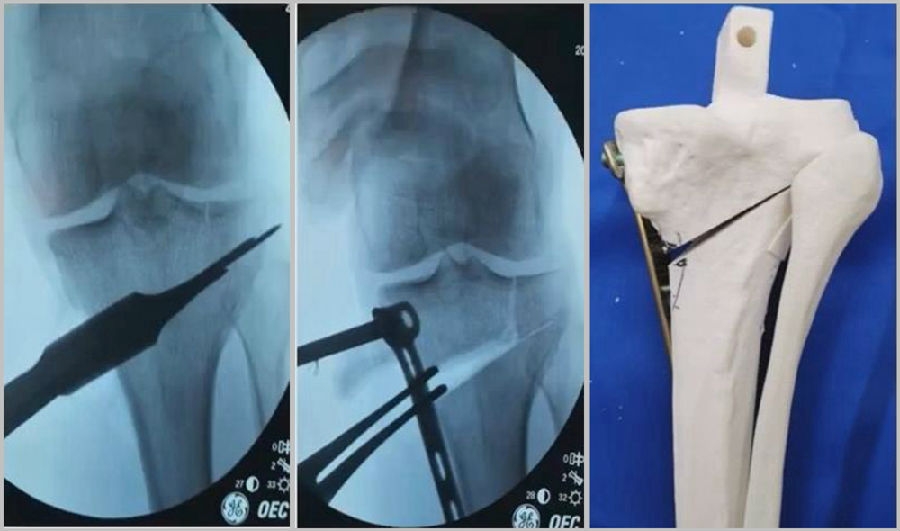

(1)合页位置

合页的位置应放置在腓骨头尖,距离外侧平台1.5cm处。这个位置不单是骨性合页,同时也有很强的变形能力,很强的弹性,而且它周围有较多软组织合页,比如上胫腓关节、髂胫束、外侧关节囊等。

a.合理;b.过低(Ⅱ型);c.过高(Ⅰ型)

(2)合页宽度

合页具有一定的变形能力,同时还有一定的强度,一般要保留1cm左右的宽度。如果合页保留过宽,那么此时合页强度过强,而变形能力不够,在过度撑开时会出现骨折,易造成Ⅲ型骨折。如果合页保留过窄,就会容易截过了,容易出现Ⅰ型骨折。所以强调合页宽度要求要在1cm左右,这样才具有一定的稳定性,同时还有一定的变形能力。

a.合理;b.过宽(Ⅲ型);c.过窄(Ⅰ型)

(3)拉力钉技术

第3个原因和拉力钉使用技术有关。拉力螺钉的使用是希望在合页端产生一个加压的效果,如果拉力螺钉使用过度,会出现合页端拉断的情况,导致Ⅱ型骨折。所以要求拉力螺钉在使用时加压不要过度,通常当钢板有轻微的变形即可,不要过度加压。